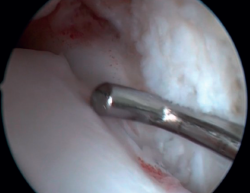

The confirmation of AAI is made by direct vision during arthroscopic examination (Figure 4). This technique allows us to visualise the entire joint, assess the state of the articular cartilage and ligaments, detect the presence of capsular adhesions, synovitis, synovial thickening, loose bodies, etc. It also allows us to carry out functional tests to reveal possible associated instabilities or to assess how the soft tissues causing pain suffer impingement. In our experience, the presence of ATFL lesions is very frequent.

Figure 4. Soft tissue anterolateral impingement in a patient with concomitant anterior talofibular ligament injury who underwent arthroscopic repair associated with resection of the impingement.